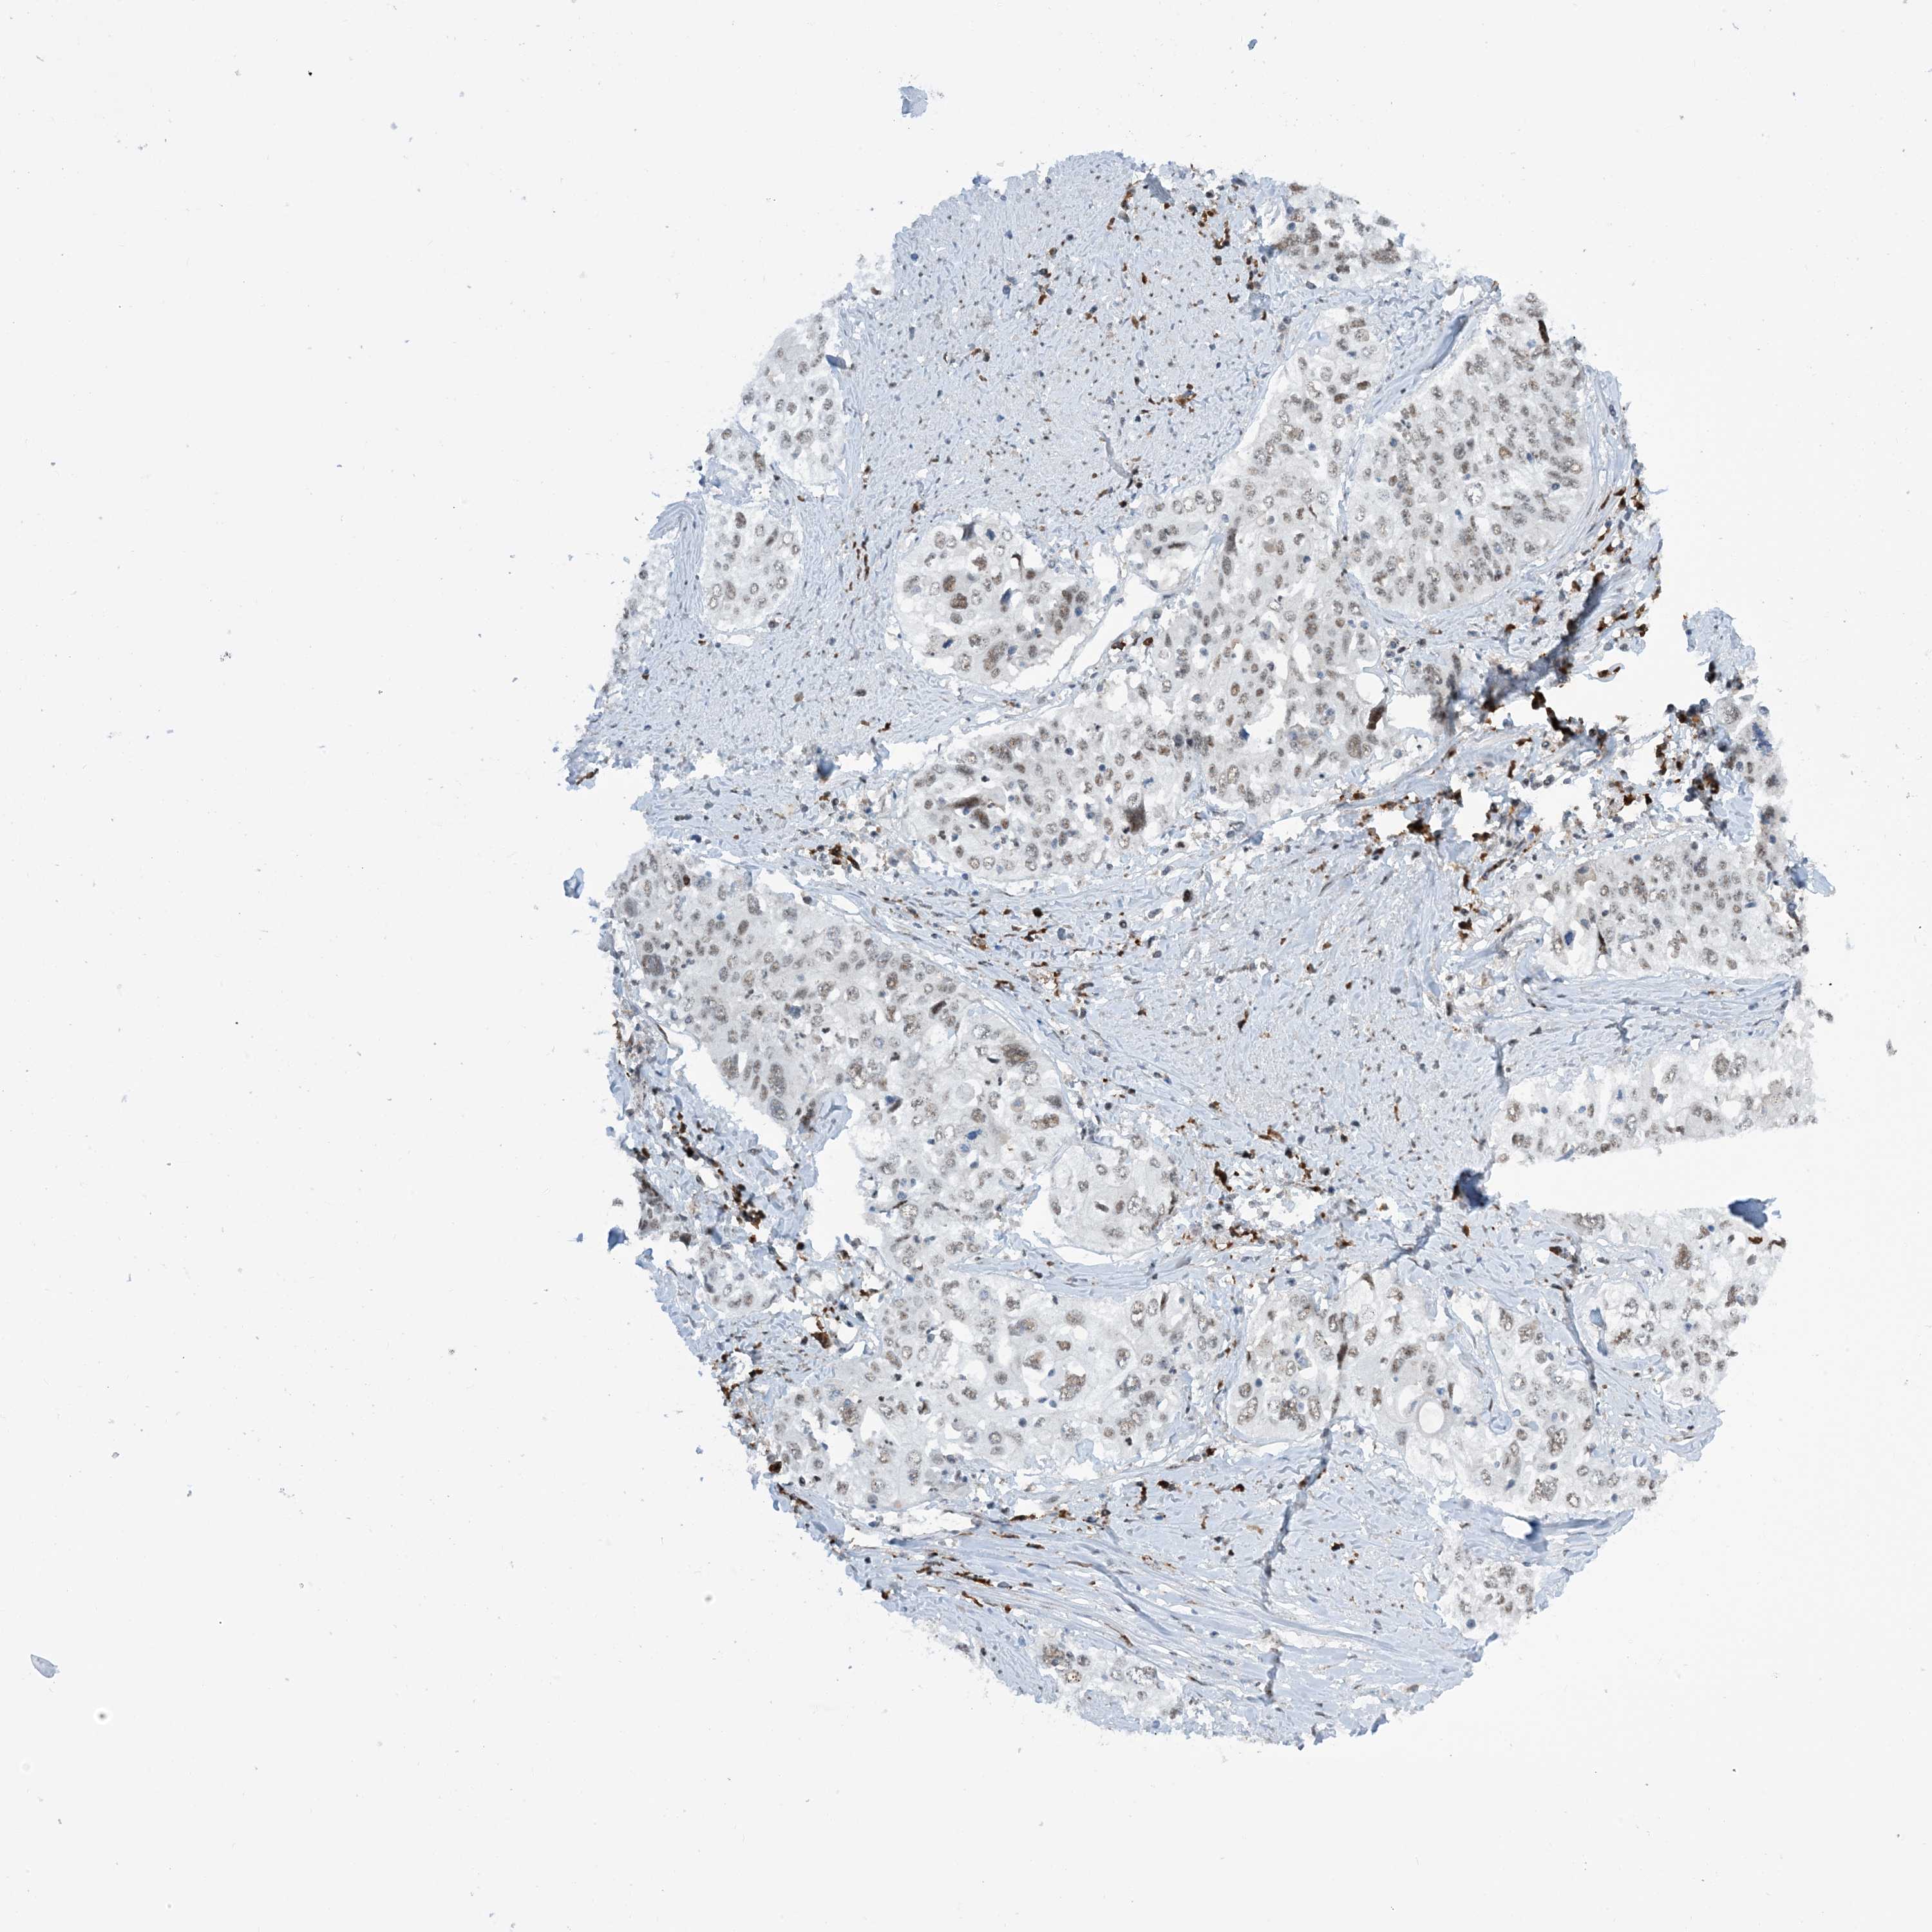

CERVICAL CANCER - Protein expressioni

A mouse-over function shows sample information and annotation data. Click on an image to view it in a full screen mode. Samples can be filtered based on level of antibody staining by selecting one or several of the following categories: high, medium, low and not detected. The assay and annotation is described here.

Note that samples used for immunohistochemistry by the Human Protein Atlas do not correspond to samples in the TCGA dataset.

Antibody stainingi

Antibody staining in the annotated cell types in the current human tissue is reported as not detected, low, medium, or high, based on conventional immunohistochemistry profiling in selected tissues. This score is based on the combination of the staining intensity and fraction of stained cells.

Each image is clickable and will lead to virtual microscopy that enables deeper exploration of all samples and also displays staining intensity scores, fraction scores and subcellular localization as well as patient and tissue information for each sample.

Antibody HPA034701

Antibody HPA034702

Staining

High

Medium

Low

Not detected

Intensity

Strong

Moderate

Weak

Negative

Quantity

>75%

75%-25%

<25%

None

Location

Nuclear

Cytoplasmic/membranous

Cytoplasmic/membranous,nuclear

Squamous cell carcinoma, NOS

Adenocarcinoma, NOS